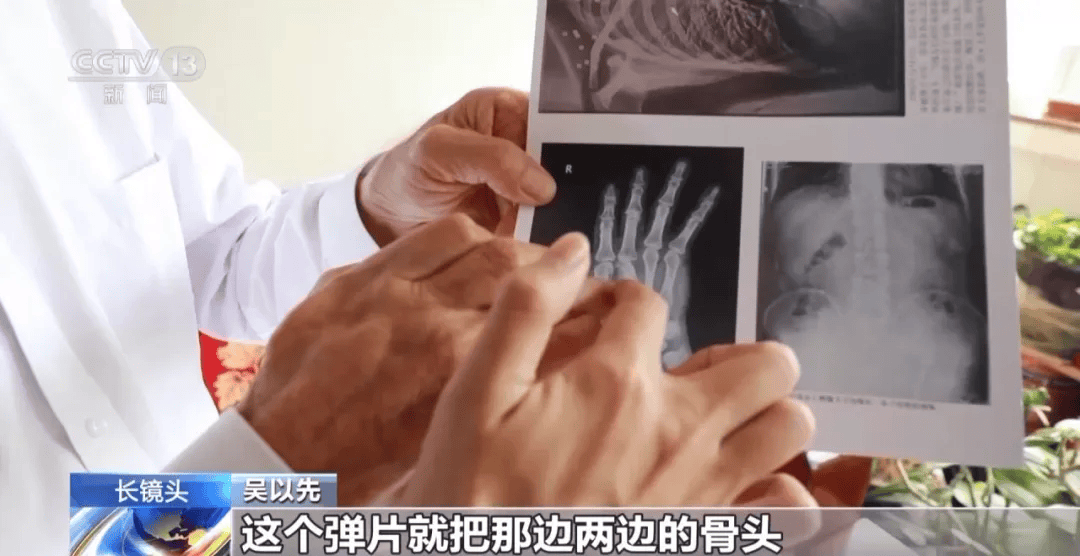

当时,子弹把他的小腹打穿了

被打穿的右手康复后也是扭曲的

但是吴以先的右手落下了残疾